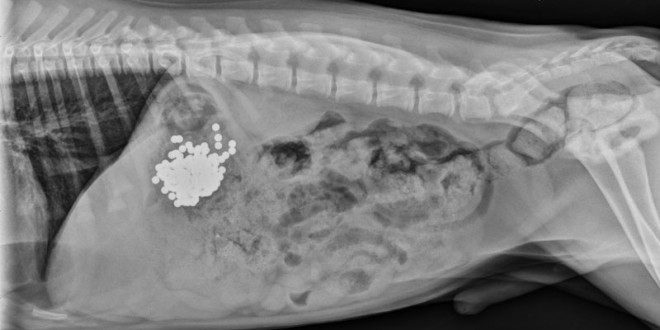

收好你的襪子、黃色小鴨跟燈泡!不然它們會出現在你家毛小孩胃裡!